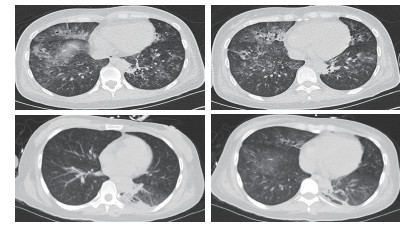

患者女性,29岁,以“恶心、呕吐1个月余,进食困难伴饮水呛咳半月,呼吸困难5 d,发热1 d”主诉收入北京世纪坛医院。患者病史长且复杂,笔者根据其先后就诊医院对其病史进行总结(表 1)。2018年5月10日患者在北京西客站候车过程中出现呼吸困难加重,随后出现呼之不应,立即送至本院急诊。至本院急诊抢救室时,患者生命体征心律166次/min,呼吸32次/min,血压80/47 mmHg(1 mmHg=0.133 kPa),氧饱和度80%,体温39.5℃,查体:浅昏迷,双瞳孔等大正圆,直径约2 mm,对光反射存在,无颈项强直,口周及口腔内可见较多清亮唾液,双肺呼吸音粗,双肺可闻及少量湿性啰音,左下肺为著,心律齐,各瓣膜听诊区未及杂音。腹部查体未见异常。双侧腱反射存在,双侧病理征阴性。血气:pH 6.95, PCO2 88 mmHg, PO2 48 mmHg, Lac 8.0 mmol/L, 故立即予气管插管、呼吸机辅助通气, 建立静脉通路补液及去甲肾上腺素泵入升压治疗,并立即收入本院急诊ICU。患者入院后主要血化验结果见表 2。心脏彩超提示弥漫性室壁运动异常,EF为45%,考虑感染相关心肌抑制。胸部CT提示双肺弥漫大小不等点片、斑片状高密度影,其内可见支气管走行,纵隔内可见多个大小不等淋巴结影,考虑双肺感染(图 1)。下肢血管超声、头颅CT、腹部CT均未见明显异常。患者入院后继续予气管插管接呼吸机辅助通气,呼吸机模式PC,起始参数:P 18 cmH2O(1 cmH2O=0.098 kPa),f 14次/min,PEEP 4 cmH2O,FiO2 40%;去甲肾上腺素静脉泵入及静脉补液升压治疗;肠内营养治疗;结合患者胸部CT及其他化验结果,诊断首先考虑重症肺炎,脓毒症,脓毒性休克,Ⅱ型呼吸衰竭,因此抗感染采用联合抗细菌、真菌及病毒全覆盖方案,同时予静脉输注人免疫球蛋白(IVIg)20 g/d ×5 d,静脉输注甲泼尼龙80 mg/12 h×4 d→40 mg/12 h×7 d→40 mg/d×3 d→甲泼尼龙片20 mg/d口服。经过上述治疗,患者体温逐渐下降至正常,神志逐渐转清,四肢肌力逐渐恢复至正常,呼吸机条件逐渐下调至模式PS,参数P 8 cmH2O,FiO2 40%,循环逐渐稳定并停用血管活性药物。复查主要血化验结果(表 3)均较前好转。抗感染治疗后前后2次复查胸部CT均提示肺炎较前吸收好转(图 2)。此时患者能脱机,但却不能拔管,且患者无咳嗽反射亦不能遵嘱吞咽。

图 2 患者治疗后复查胸部CT检查结果(上下分别为患者治疗8 d和13 d情况)